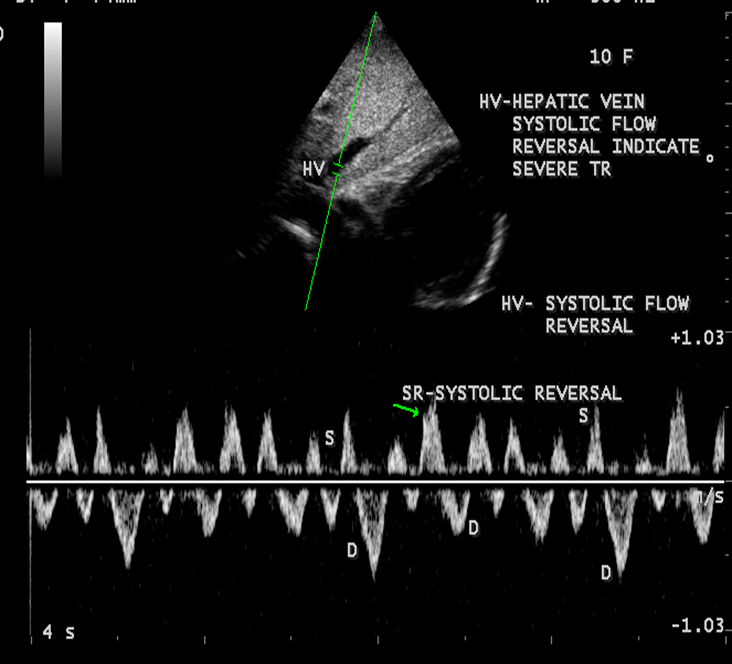

Normal hepatic vein flow travels _____ from the transducer towards the IVC and is encoded in _____

away/ blue.

TR flowing into the IVC & Hepatic veins will flow ______ the transducer during systole and is encoded in _____

towards/red

On the spectral waveform, this systolic flow will appear _____ the baseline (______)

(color & spectral flow reversal of the hepatic veins)

above/ antegrade

The hepatic vein waveform can be reflective of the ______

severity of TR present.

The more severe the regurgitation, the more _______ the hepatic waveform becomes.

pulsatile

anything above baseline means flow reversal

How to prove severe TR